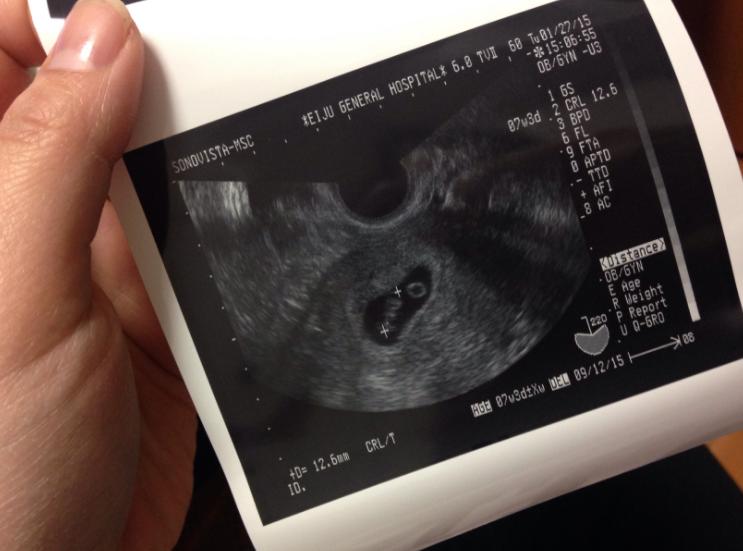

一般来讲,女性在发现停经之后,可以做验尿或验血检测hcg数值,来确定怀孕,在怀孕40天左右可以做B超看到孕囊,在怀孕7-8周左右能看到明显的胎心和胎芽。

正常情况下,怀孕7-8周左右可以看到原始心管搏动和胎芽,但是如果超过10周还未出现,胎心,那极有可能是“胎儿停育”的情况。

那这时候可以去做B超,医生也会以B超检查为主要诊断依据,如果连续两周检查,没有发现孕囊增大,并且大小与妊娠周数不符,就要考虑是否是“胎停育”。